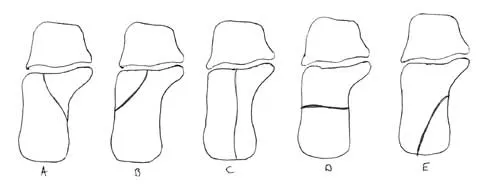

In Figure 14, the primary fracture line in a calcaneal fracture is best depicted by which of the following schematics?